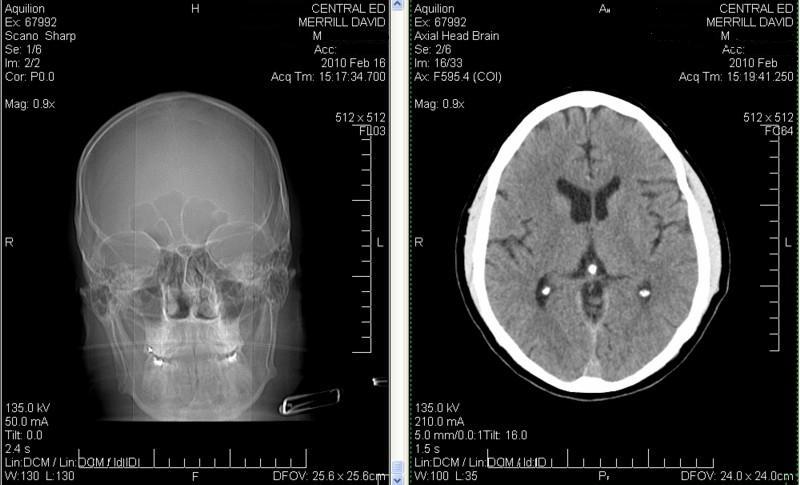

Click image for larger version

Name:	CAT Scan three stones sanitized.JPG

Views:	4

Size:	50.9 KB

ID:	42344

Really folks! Is this brain science? Look at that... If you are willing to put some humor up your nose it only costs $1!

Scanning my head topographically it becomes obvious how close the air is getting to my pineal gland, now that I have cleared out all the snot. It took about six weeks - about six years ago. And I even noticed some cottony deposits loosened up recently. Few people realize they are carrying around a low-grade sinus infection. - I suspect that some of the snot and bacteria has been up people's noses since childhood!

Name:	CAT Scan Pineal Gland.jpg

Views:	1

Size:	175.7 KB

ID:	42345